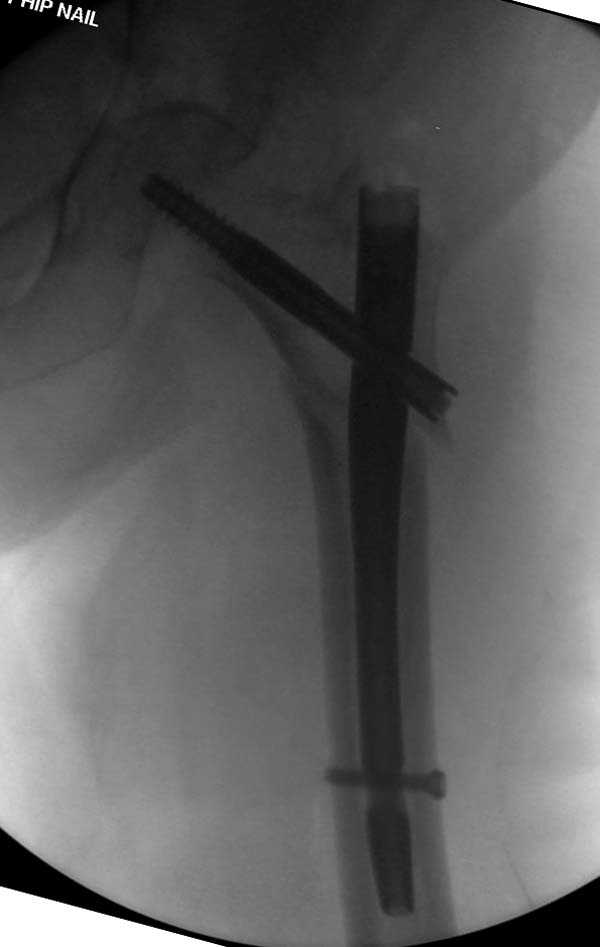

Здесь представлен случай, где в послеоперационном периоде обнаружена техническая ошибка, Gamma 3 установлен с нарушением методики. Больная в 91 лет, прооперирована через день после поступления и выписана через 48 часов.

При первом послеоперационном поликлиническом осмотре больная предъявила жалобы на боли в бедре. В серийных снимках обнаружен продольный перелом верхнего отдела бедра.

Считаем, что техническая ошибка произошла во время установки гвоздя, когда рассверливанию канала не уделили должного внимания. Канал остался узковат, и гвоздь был забит с силой. Полная нагрузка конечности приостановлена на две недели, и боли в конечности изчезли. Больная начала нагрузку и перелом срастается.-- Djoldas Kuldjanov, M.D.Associate ProfessorDepartment of Orthopedic SurgerySt. Louis University